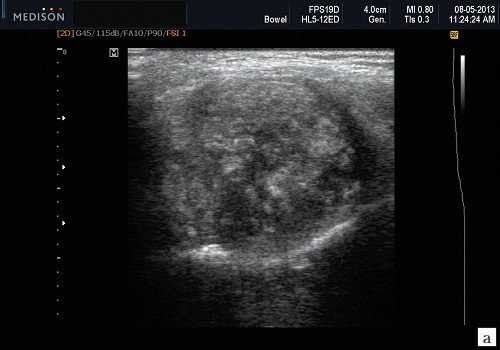

Плеоморфная (полиморфная) аденома (смешанная опухоль СЖ) - аденома СЖ, построенная из двух типов клеток: эпителия протоков и миоэпителиоцитов. Макроморфологическая картина. Опухоль обычно представляет собой эластичный или плотный узел дольчатой серовато-белой ткани, как правило, инкапсулированный частично. Типичной для плеоморфной аденомы является так называемая хондроидная строма, напоминающая гиалиновый хрящ. Варианты эхографического изображения плеоморфных аденом представлены на рисунке 8.

Рис. 8. Плеоморфная аденома СЖ.